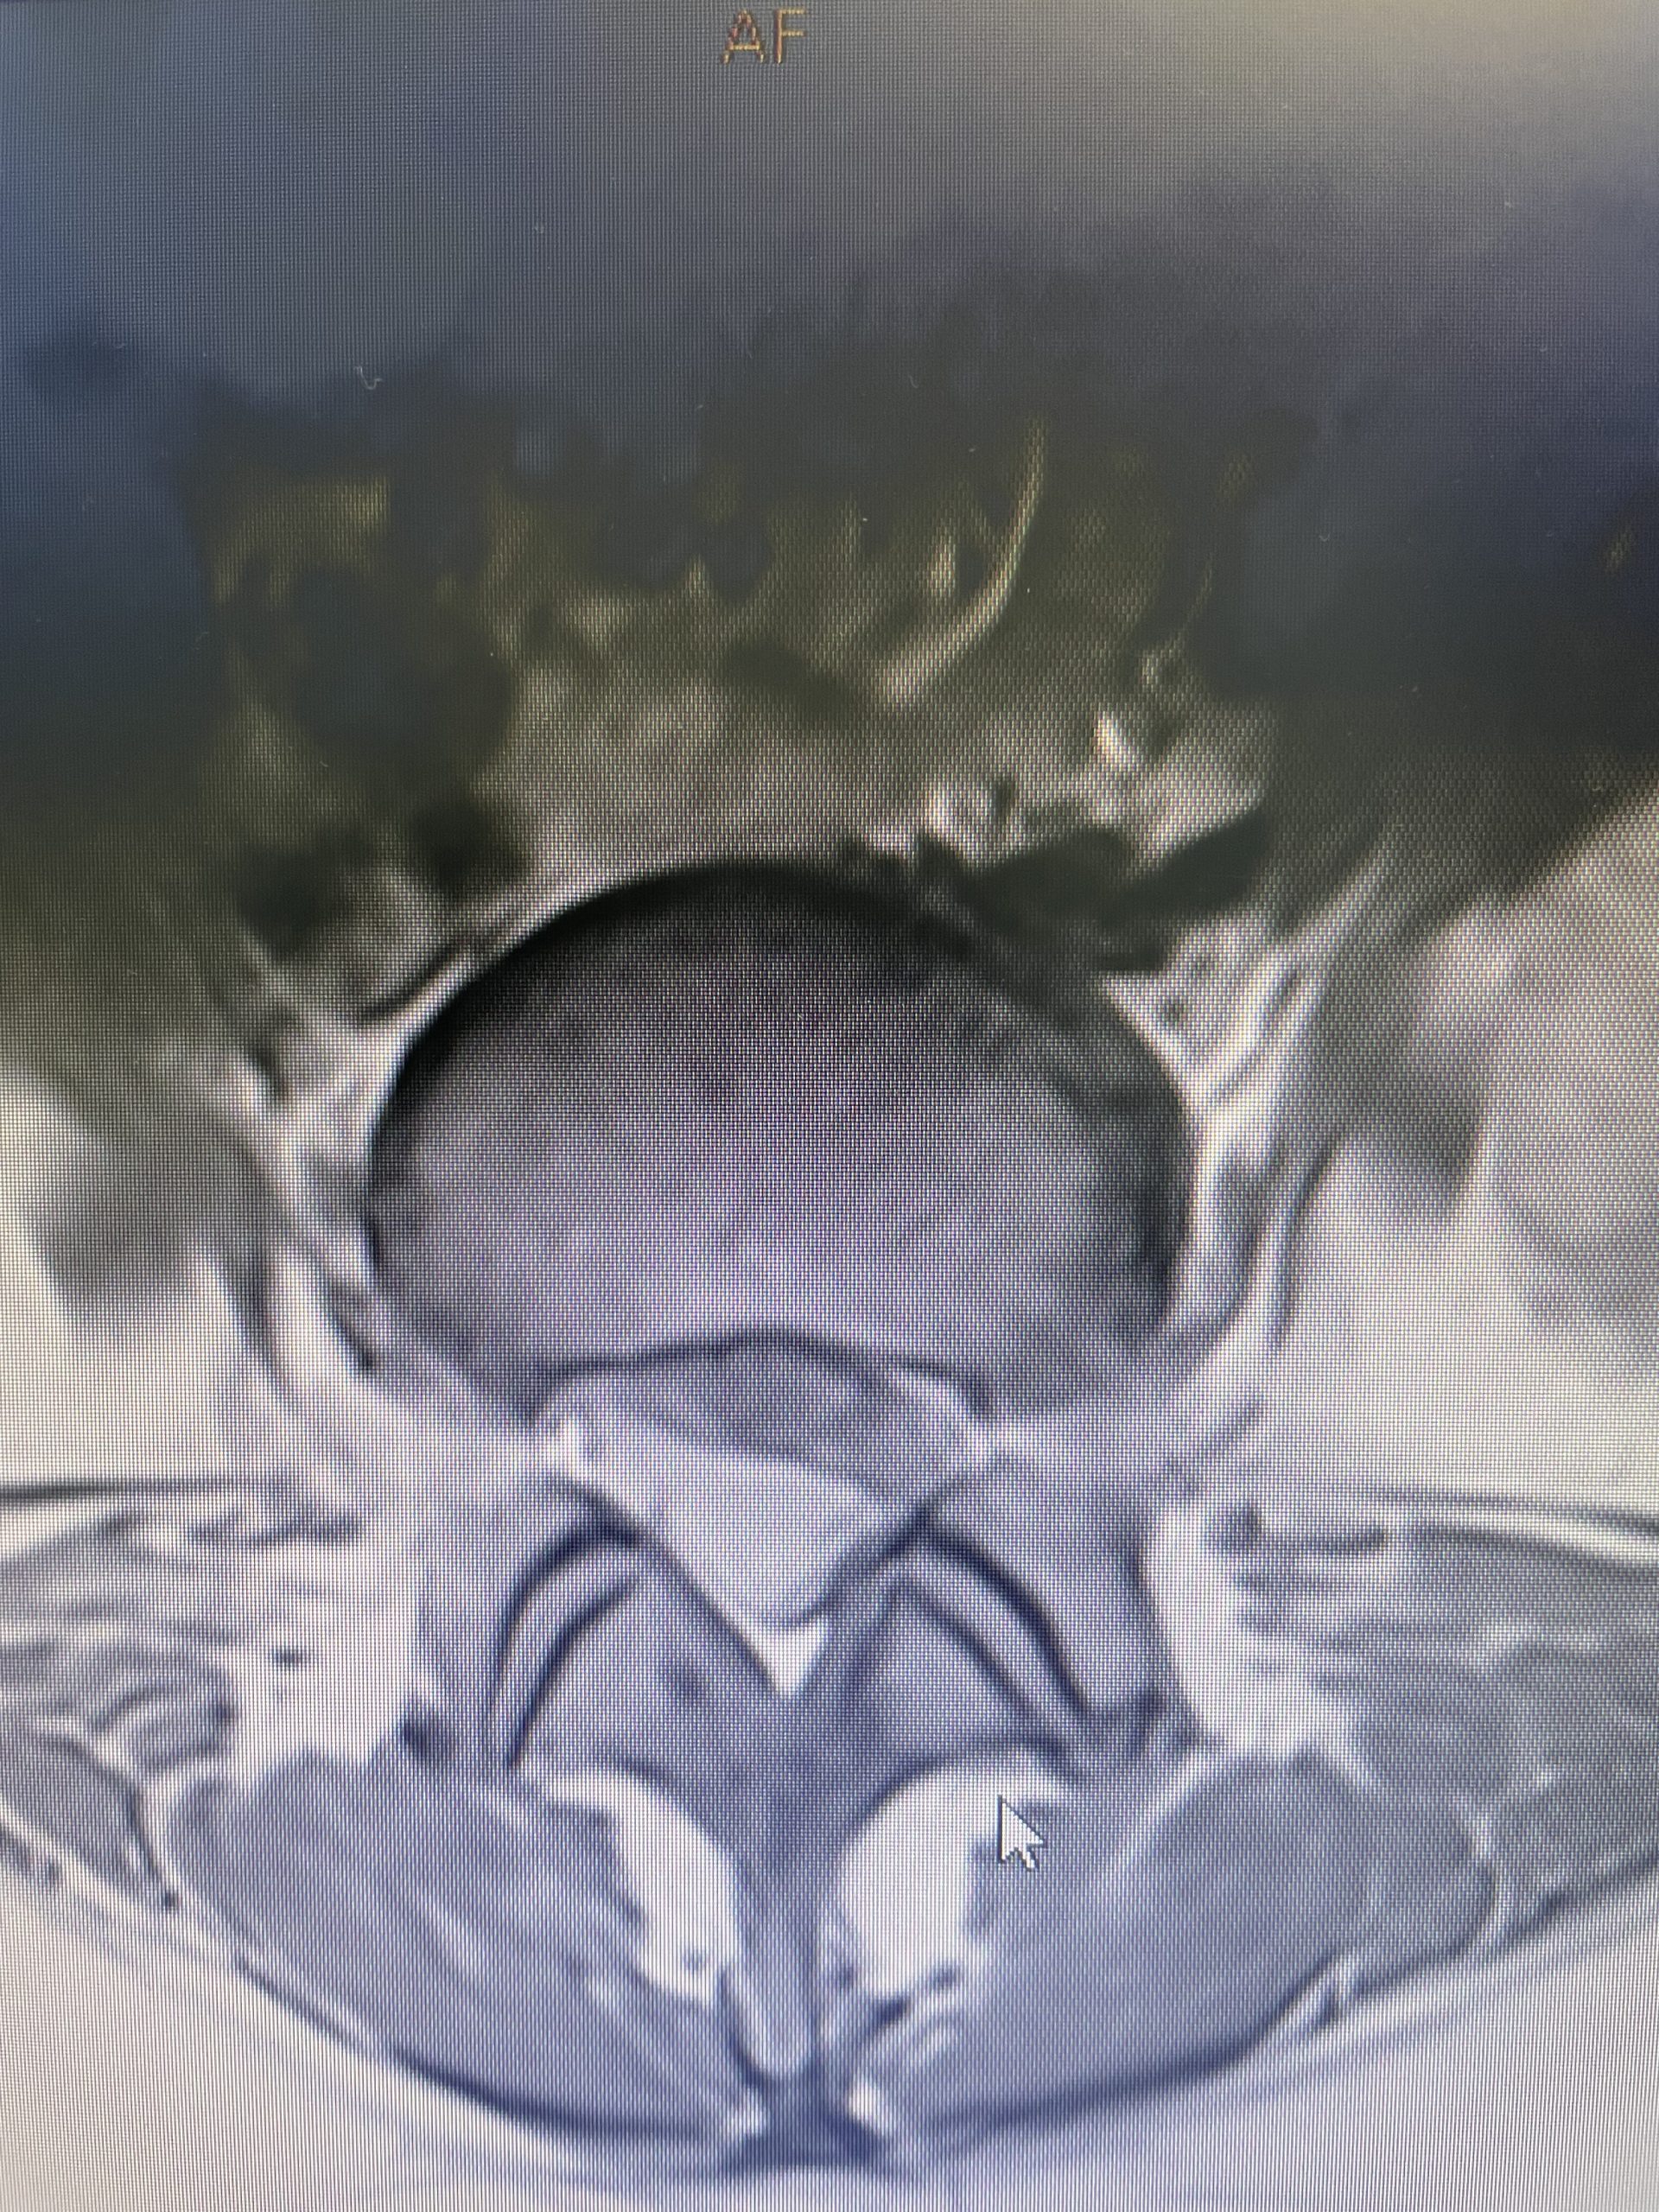

A 69-year-old male presents with chronic low back pain that seems to improve with sitting. The patient had had a prior laminectomy for severe stenosis and in situ fusion five years prior which means that we used bone graft to perform the fusion but no instrumentation. He had done well. Over the last year or so he developed low back pain but no leg pain. The patient had tried all means of conservative management including physical therapy, chiropractic care, acupuncture and epidural injections. Neurologically he was intact. MRI revealed significant stenosis at L2-3 above his prior laminectomy and fusion (Fig 1). We discussed options including surgery. One of the problems we face is a patient with severe stenosis that has severe low back pain with no leg pain. This is particularly challenging when the back pain goes away in flexion or sitting. The quandary is that anecdotally patients with these specific symptoms do tend to improve their back pain after laminectomy, although there are no good studies to support this. Patients with classic neurogenic claudication with pain down their legs when they walk and improved when they sit have a better chance of success. Subjecting a patient to laminectomy for just back pain in the face of having prior surgery puts the patient at risk for not only a potential dural leak because of scarring, but also there may be less of a chance of relieving the back pain than if the patient has leg symptoms. After a discussion, since the patient for the most part is able to manage with conservative treatment modalities is just wait and see over the next three months.